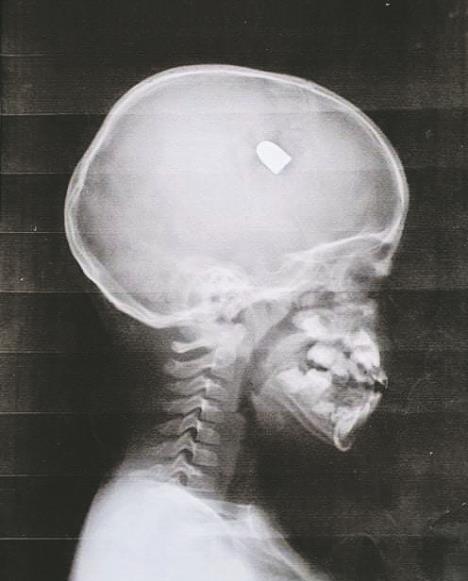

Ne gubeći vreme, odmah je sa sinom krenula ka bolnici, gde je dečak podvrgnut detaljnim pregledima. Na rendgenskom snimku se jasno ukazao metak u dečakovoj glavi. Doktori su bili šokirani, baš kao i dečakovi roditelji. Kako operaciju nije bilo moguće odmah izvršiti, dečak je stavljen u veštačku komu, dok su njegovi roditelji prikupili dovoljno novca da se izvrši komplikovana operacija vađenja metka iz Adrijanove glave.